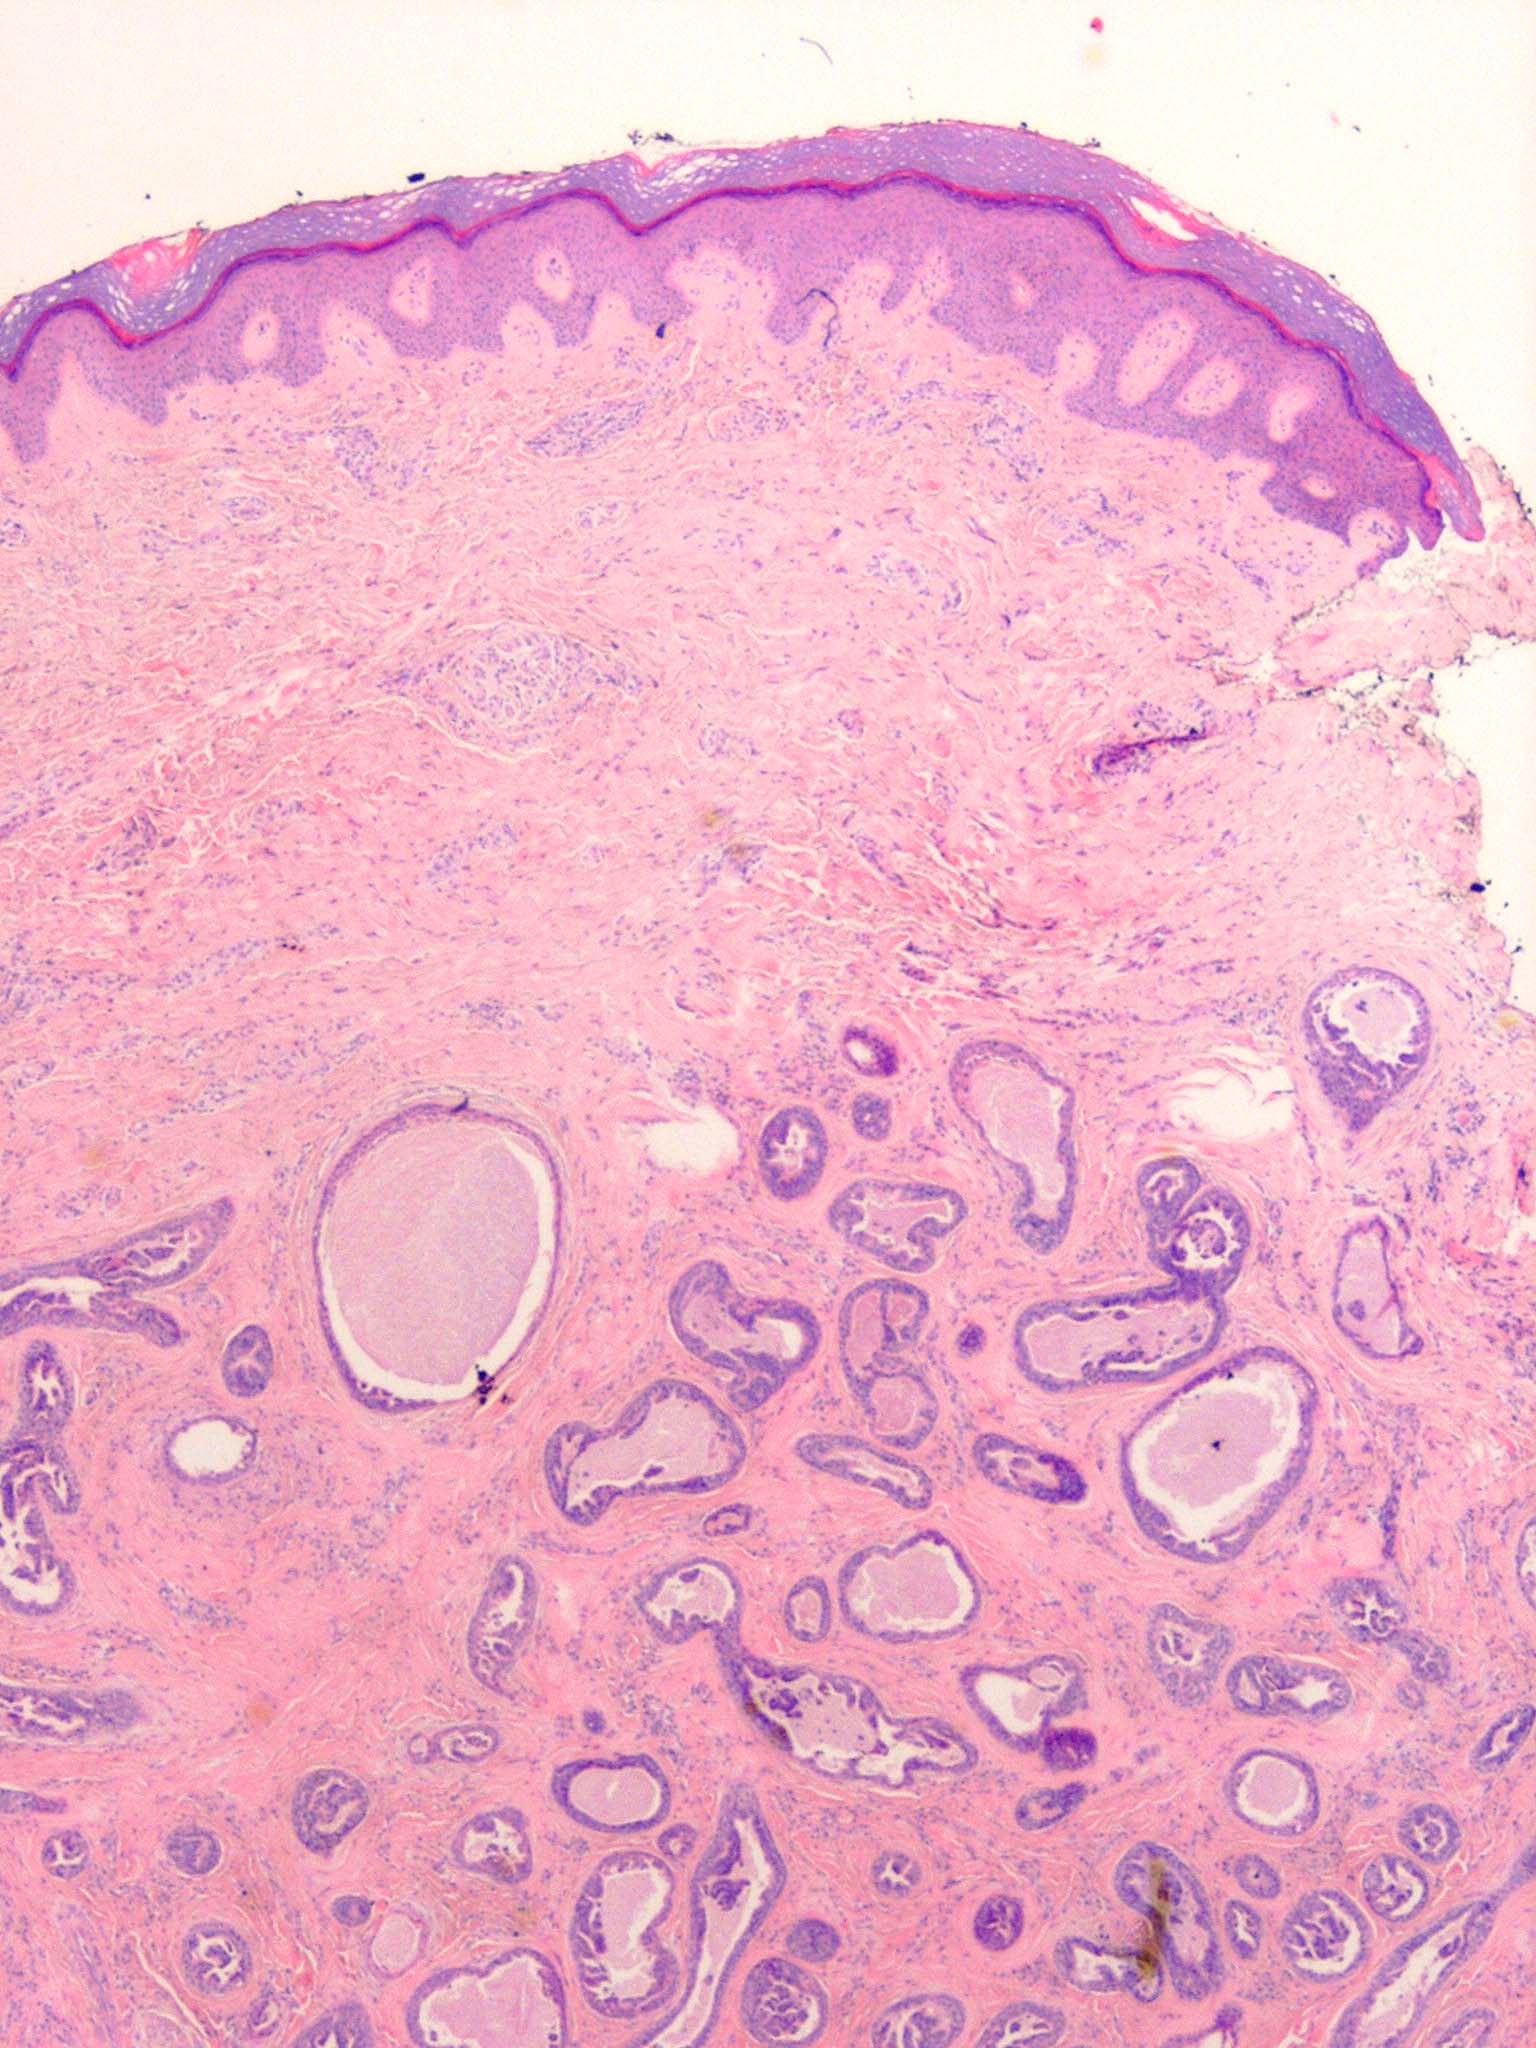

Papillary eccrine adenoma = الغدوم الناتح الحطاطي